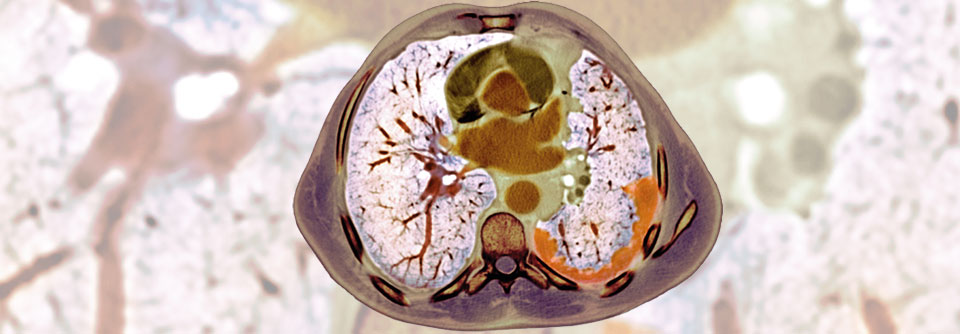

Immuncheckpoint-Inhibitoren haben sich bei der Behandlung des nicht-resektablen Pleuramesothelioms weitgehend bewährt. Immuncheckpoint-Inhibitoren haben sich bei der Behandlung des nicht-resektablen Pleuramesothelioms weitgehend bewährt. © chokniti – stock.adobe.com

In der Therapie des malignen, nicht-resektablen Pleuramesothelioms steht eine neue Therapieoption in den Startlöchern. Immuncheckpoint-Inhibitoren haben sich auch in dieser Indikation als effektiv erwiesen.

Das maligne Pleuramesotheliom ist ein hochaggressiver, zum Diagnosezeitpunkt meist inoperabler Tumor. Weniger als 10 % der Betroffenen überleben länger als fünf Jahre. Bis vor Kurzem stellte die Chemotherapie mit einem Platin plus Pemetrexed den Standard in der Erstlinie dar. Im Oktober vergangenen Jahres wurde zumindest in den USA die Kombination zweier Immuncheckpoint-Inhibitoren, Nivolumab plus Ipilimumab, für die Behandlung des nicht mehr resezierbaren Tumors zugelassen. Beide Antikörper hatten sich im Rahmen einer Phase-3-Studie bezüglich der Überlebensprognose als überlegen erwiesen.